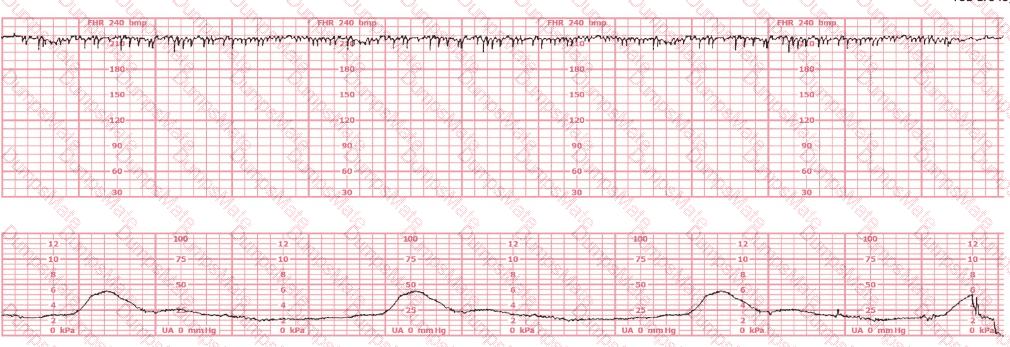

This fetal heart rate tracing is obtained upon the woman's admission to labor and delivery. This tracing is most reflective of:

EFM Question 5